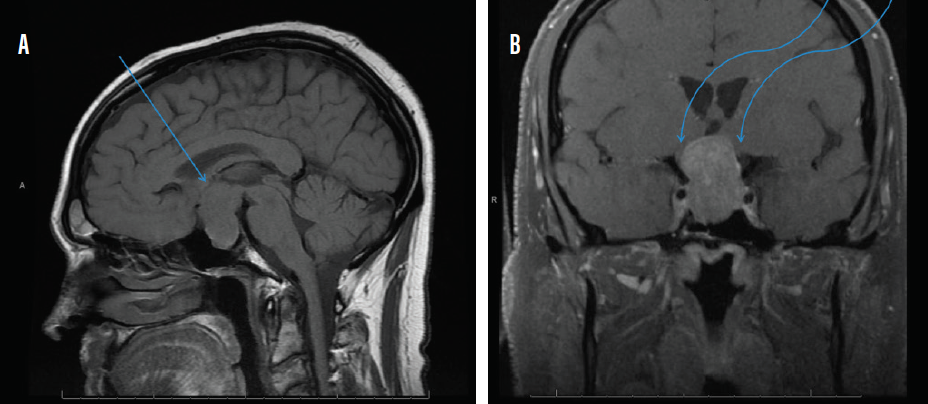

MRI with and without contrast of the brain and/or orbits with attention to the sella is the recommended medium for diagnosis (Figure 2). A patient with a confirmed pituitary macroadenoma should be referred to both neurosurgery and endocrinology. Asymptomatic patients with incidental macroadenomas should receive continued ophthalmologic surveillance because any new visual symptoms strongly indicate a need for surgical intervention. Although there are no established guidelines for the length of ophthalmologic follow-up, lesion size and a progression of visual field defects should inform decisions regarding timeline.

Figure 2. Sagittal midline precontrast T1-weighted MRI showing enlargement of the sella turcica and superior extension of a pituitary macroadenoma (arrow, A). Coronal T1-weighted MRI with contrast showing the optic chiasm stretched and compressed over the mass (arrows, B).